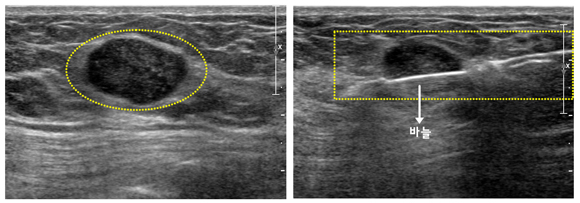

총생검 초음파 사진과 총생검 시술 사진

세침흡인 세포검사 초음파 사진과 세침흡인 세포검사 시술 사진